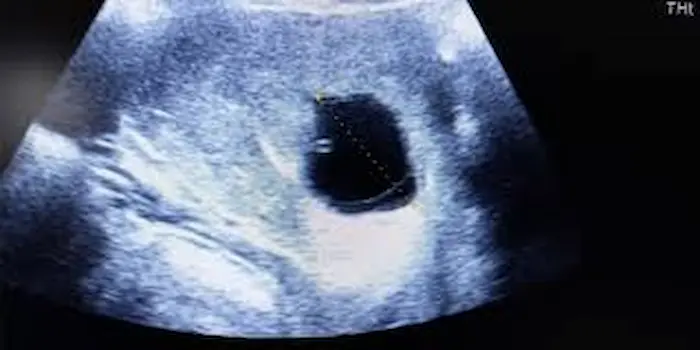

عدم نمو الجنين داخل كيس الحمل هو ما يعرف طبيًا باسم الحمل اللاجنيني أو البويضة التالفة Blighted ovum، ومعناه أن كيس الحمل يتكون داخل الرحم بشكل طبيعي في بدايته، لكن الجنين نفسه لا ينمو بداخله أو يتوقف نموه في وقت مبكر جدًا، بحيث يظهر الكيس فارغًا عند إجراء السونار، يحدث عادةً في الأسابيع الأولى من الحمل أي بين الأسبوع الخامس والعاشر.

- في الأسبوع السادس إلى الثامن حيث إنه عند عمل السونار يفترض ظهور الجنين مع النبض، وإذا كان الكيس فارغًا أو فيه كيس بدون جنين يبدأ الطبيب بالشك في الحمل اللاجنيني.

- إذا ظل الكيس فارغًا حتى الأسبوع التاسع أو العاشر بدون جنين أو نبض، يتم تشخيص الحالة بشكل شبه مؤكد.

- يعد الوسيلة الأساسية حيث يفترض رؤية الجنين وسماع نبضه، ابتداءً من الأسبوع السادس تقريبًا.

- إذا ظهر كيس الحمل فارغاً أو كان جنين بلا نبض بعد مرور الوقت الكافي، يشير ذلك إلى توقف النمو.